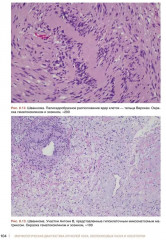

💳 Оплатить за товар можно при получении 🇰🇿 Есть бесплатная доставка по Казахстану от 1 дня 🎁 Копите бонусы с каждой покупки Настоящее руководство-атлас посвящено патоморфологической диагностике опухолей полости носа и носоглотки. Несомненным достоинством книги является систематизированное, лаконичное и вместе с тем весьма информативное изложение текстового материала (клинико-эпидемиологическая картина, морфологическая характеристика, дифференциально-диагностический ряд, необходимые дополнительные методы исследования), а так-же более 170 цветных микрофотографий наблюдений из собственной клинической практики с подробными подписями. Наряду с опухолями в книге представлен раздел наиболее часто встречающихся неопухолевых процессов синоназального тракта, необходимых для дифференциального диагноза. Руководство-атлас предлагает структурированный подход с унифицированным изложением современных данных о клинических и морфологических особенностях доброкачественных и злокачественных опухолей носа и носоглотки. |